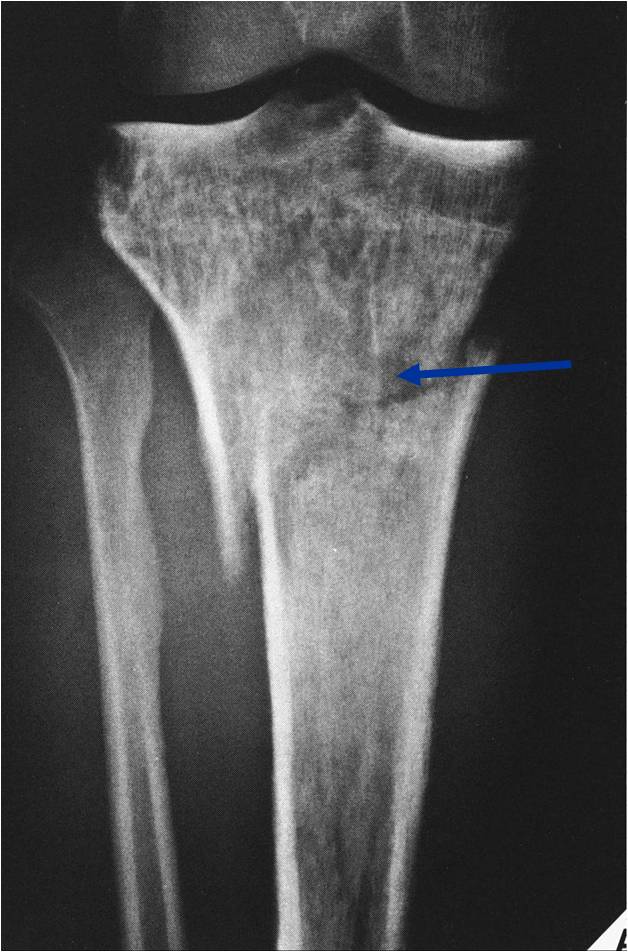

Permeative Lesion of Proximal Tibia with Pathological Fracture

- Permeative or moth eaten bone destruction (55%)

- Geographic (11%); Blow out (1%); Blastic (2%); Normal XR (5%)

- Metadiaphysis (75%)

- Periosteal reaction—may look benign

- Pathologic Fracture (22%)